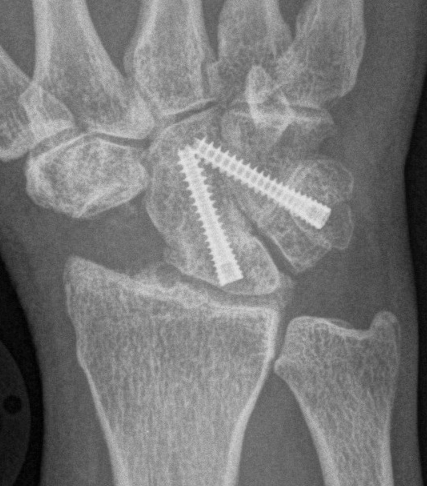

Scaphoidectomy & Limited arthrodesis

Indication

Stage II / III: Preserved radio-lunate joint

Concept scaphoidectomy + limited arthrodesis

| 4 corner fusion | 4 corner / bicolumn | 3 corner fusion | 2 corner fusion |

|---|---|---|---|

|

Capitate - lunate Triquetrum-hamate-capitate

Capitate-lunate Triquetrum-hamate |

Capitate - lunate Capitate - hamate +/- triquetrum excision |

Capitate - lunate |

Fixation options

K wires

Headless compression screws

4 corner fusion techniques

4 corner: capitate / lunate screw + triquetrum / hamate / capitate screw

Bi-column: capitate / lunate screw + triquetrum / hamate screw